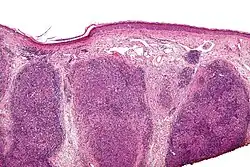

Low magnification micrograph of a lymphoepithelioma-like carcinoma showing the characteristic squamoid nests in association with clusters of lymphocytes. H&E stain.

Lymphoepithelioma-like carcinoma (LELC) is a medical term referring to a histological variant of malignant tumor arising from the uncontrolled mitosis of transformed cells originating in epithelial tissue (or in cells that display epithelial characteristics) that bear microscopic resemblance to lymphoepithelioma (nasopharyngeal carcinoma).